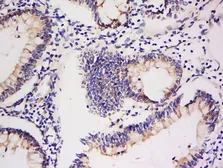

Description Rabbit MonoclonalApplications WB IHC-PReactivity Hu, RatSummary This antibody may not be suitable for rat IHC-P assay, as its rat reactivity is based on WB testing.